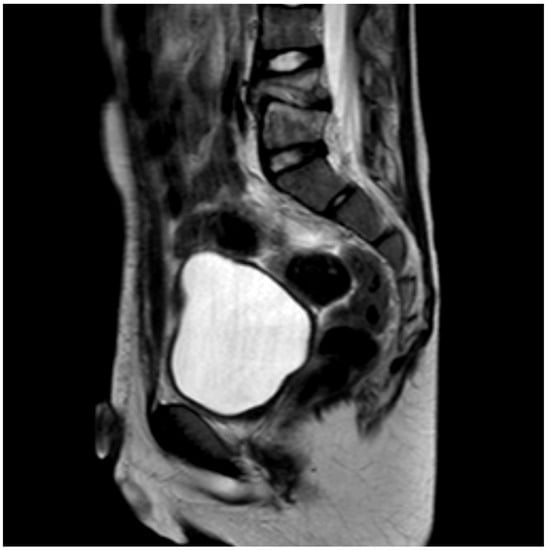

Different methods of imaging were initiated before detecting the final diagnosis of PSD: five children received a sonography of the hips and four patients an X-ray image (Figure 1) while in two cases a CT was performed. The final diagnosis was made by MR-imaging in all cases (Figure 2).

Figure 1. X-ray (sagittal view) of the lumbar spine (Pat. No. 10).